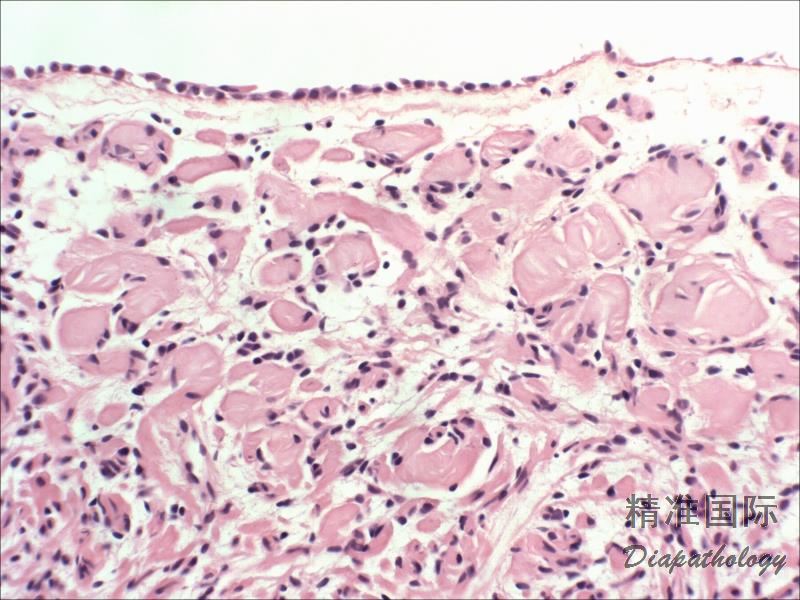

组织学表现为丛状或弥漫型两种;

丛状型几乎均与神经纤维瘤病有关,特征性表现为胶原性间质中见相互融合的梭形细胞结节;

弥漫型在黏膜固有层弥漫生长,并可扩展到肌层;

瘤细胞梭形-卵圆形,可伴有触觉小体;

部分病例细胞丰富,但细胞异型不明显,核分裂像不多,无坏死,可诊断为细胞性神经纤维瘤。